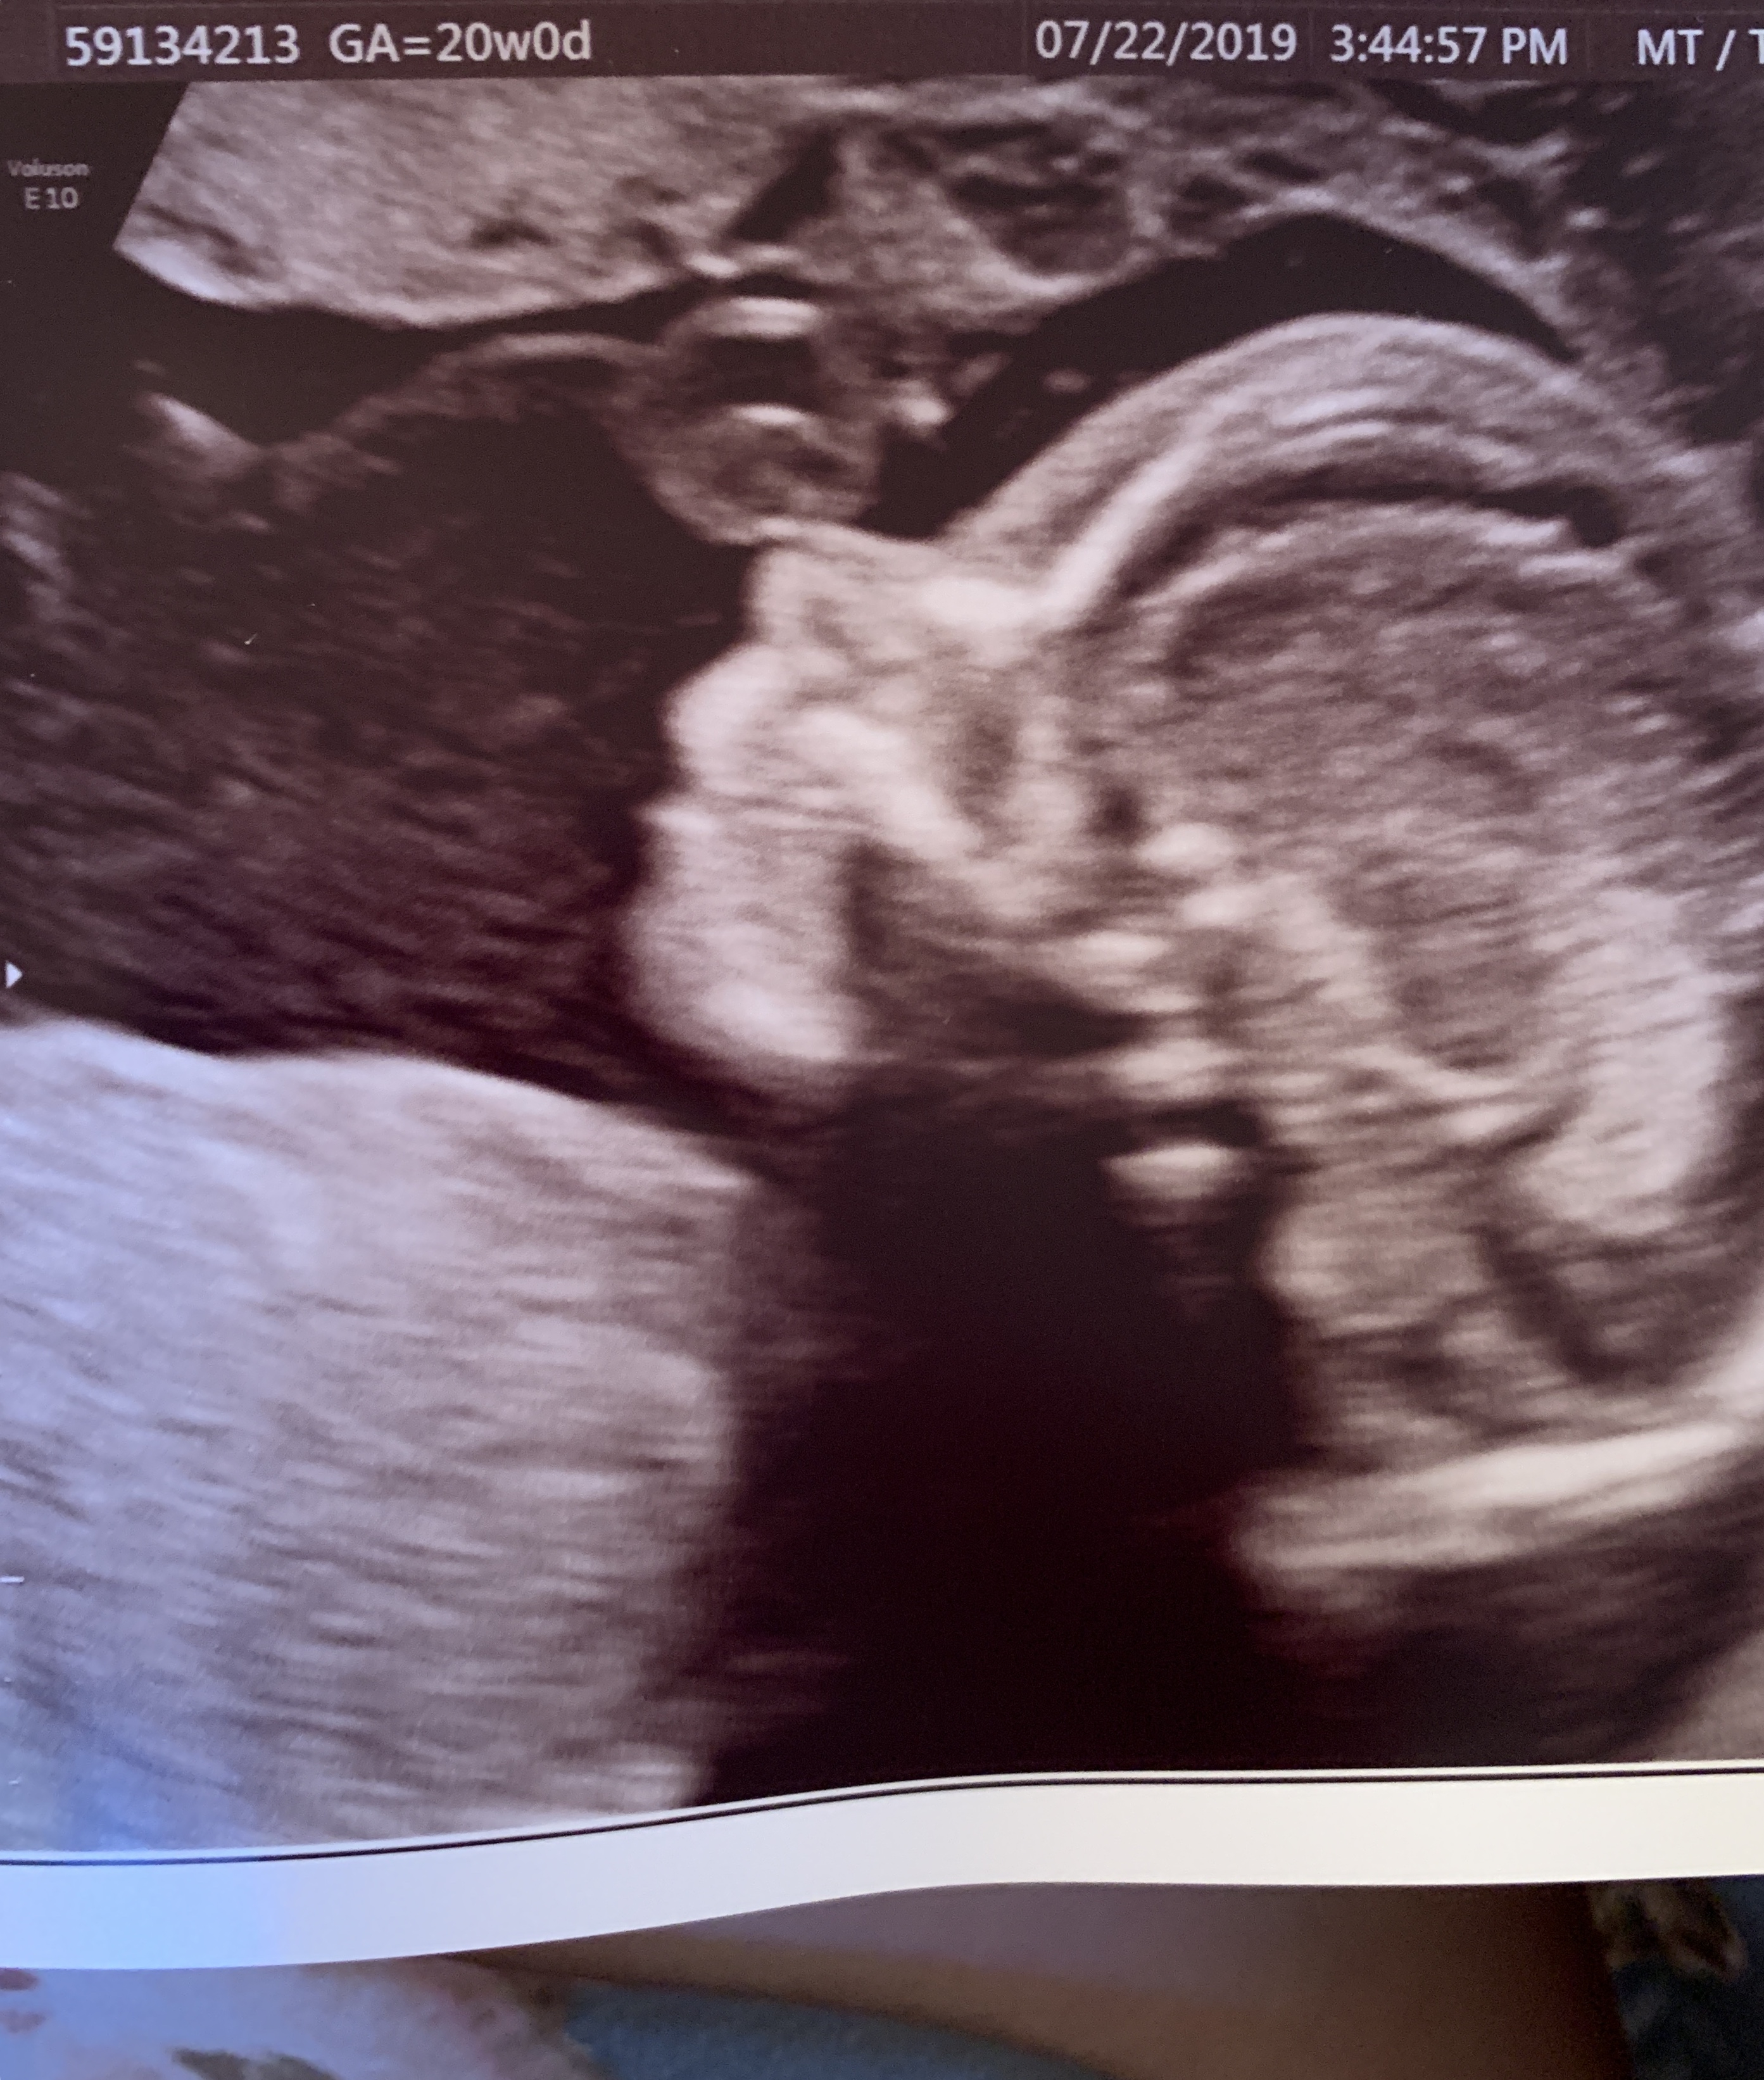

Exactly 20 weeks today. Wish we could post video here because you should’ve seen it squirm...took 90 minutes to get clear views because it flipped every 30 seconds...everything is looking good and we had no unwanted gender reveals!